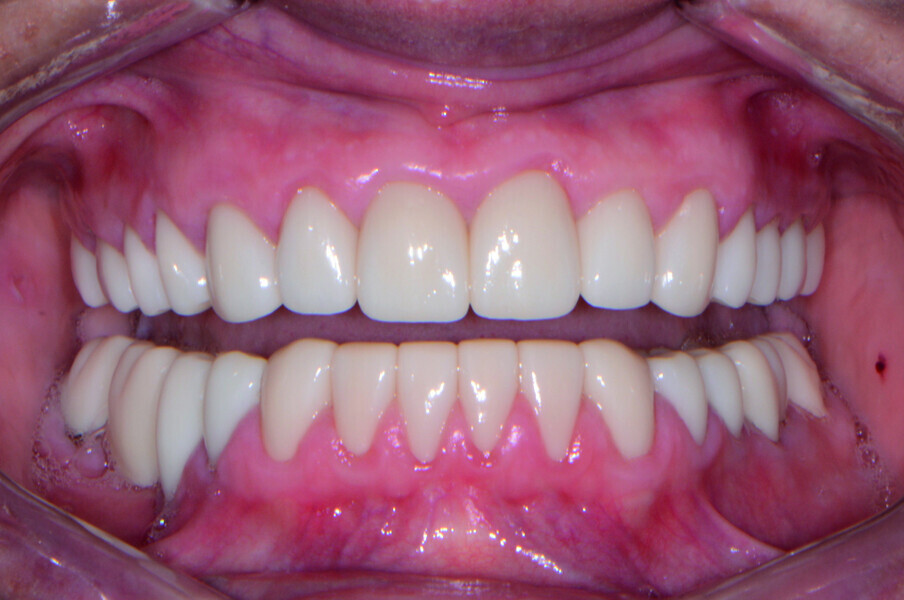

Restoring function and aesthetics with monolithic zirconia restorations